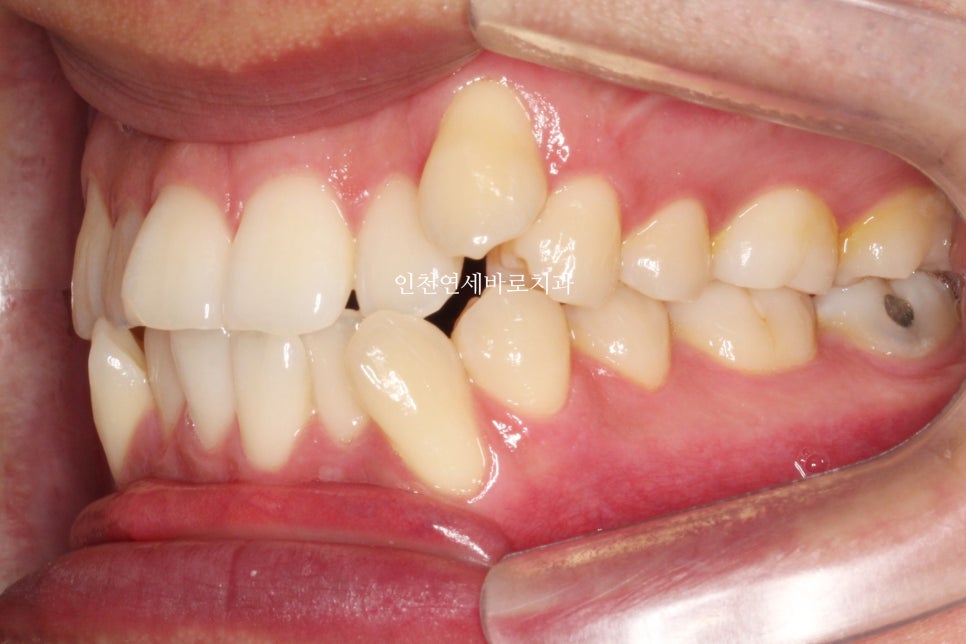

하이캐나인 이라고 불리는

위쪽 높이 위치해있는 송곳니의 교정치료의 경우, 많은 경우에 고무줄이 추가로 필요합니다.

인비절라인 자체도 열심히 껴야하지만,

이 환자분의 경우에는 12시간 정도 고무줄도 함께 착용했습니다.